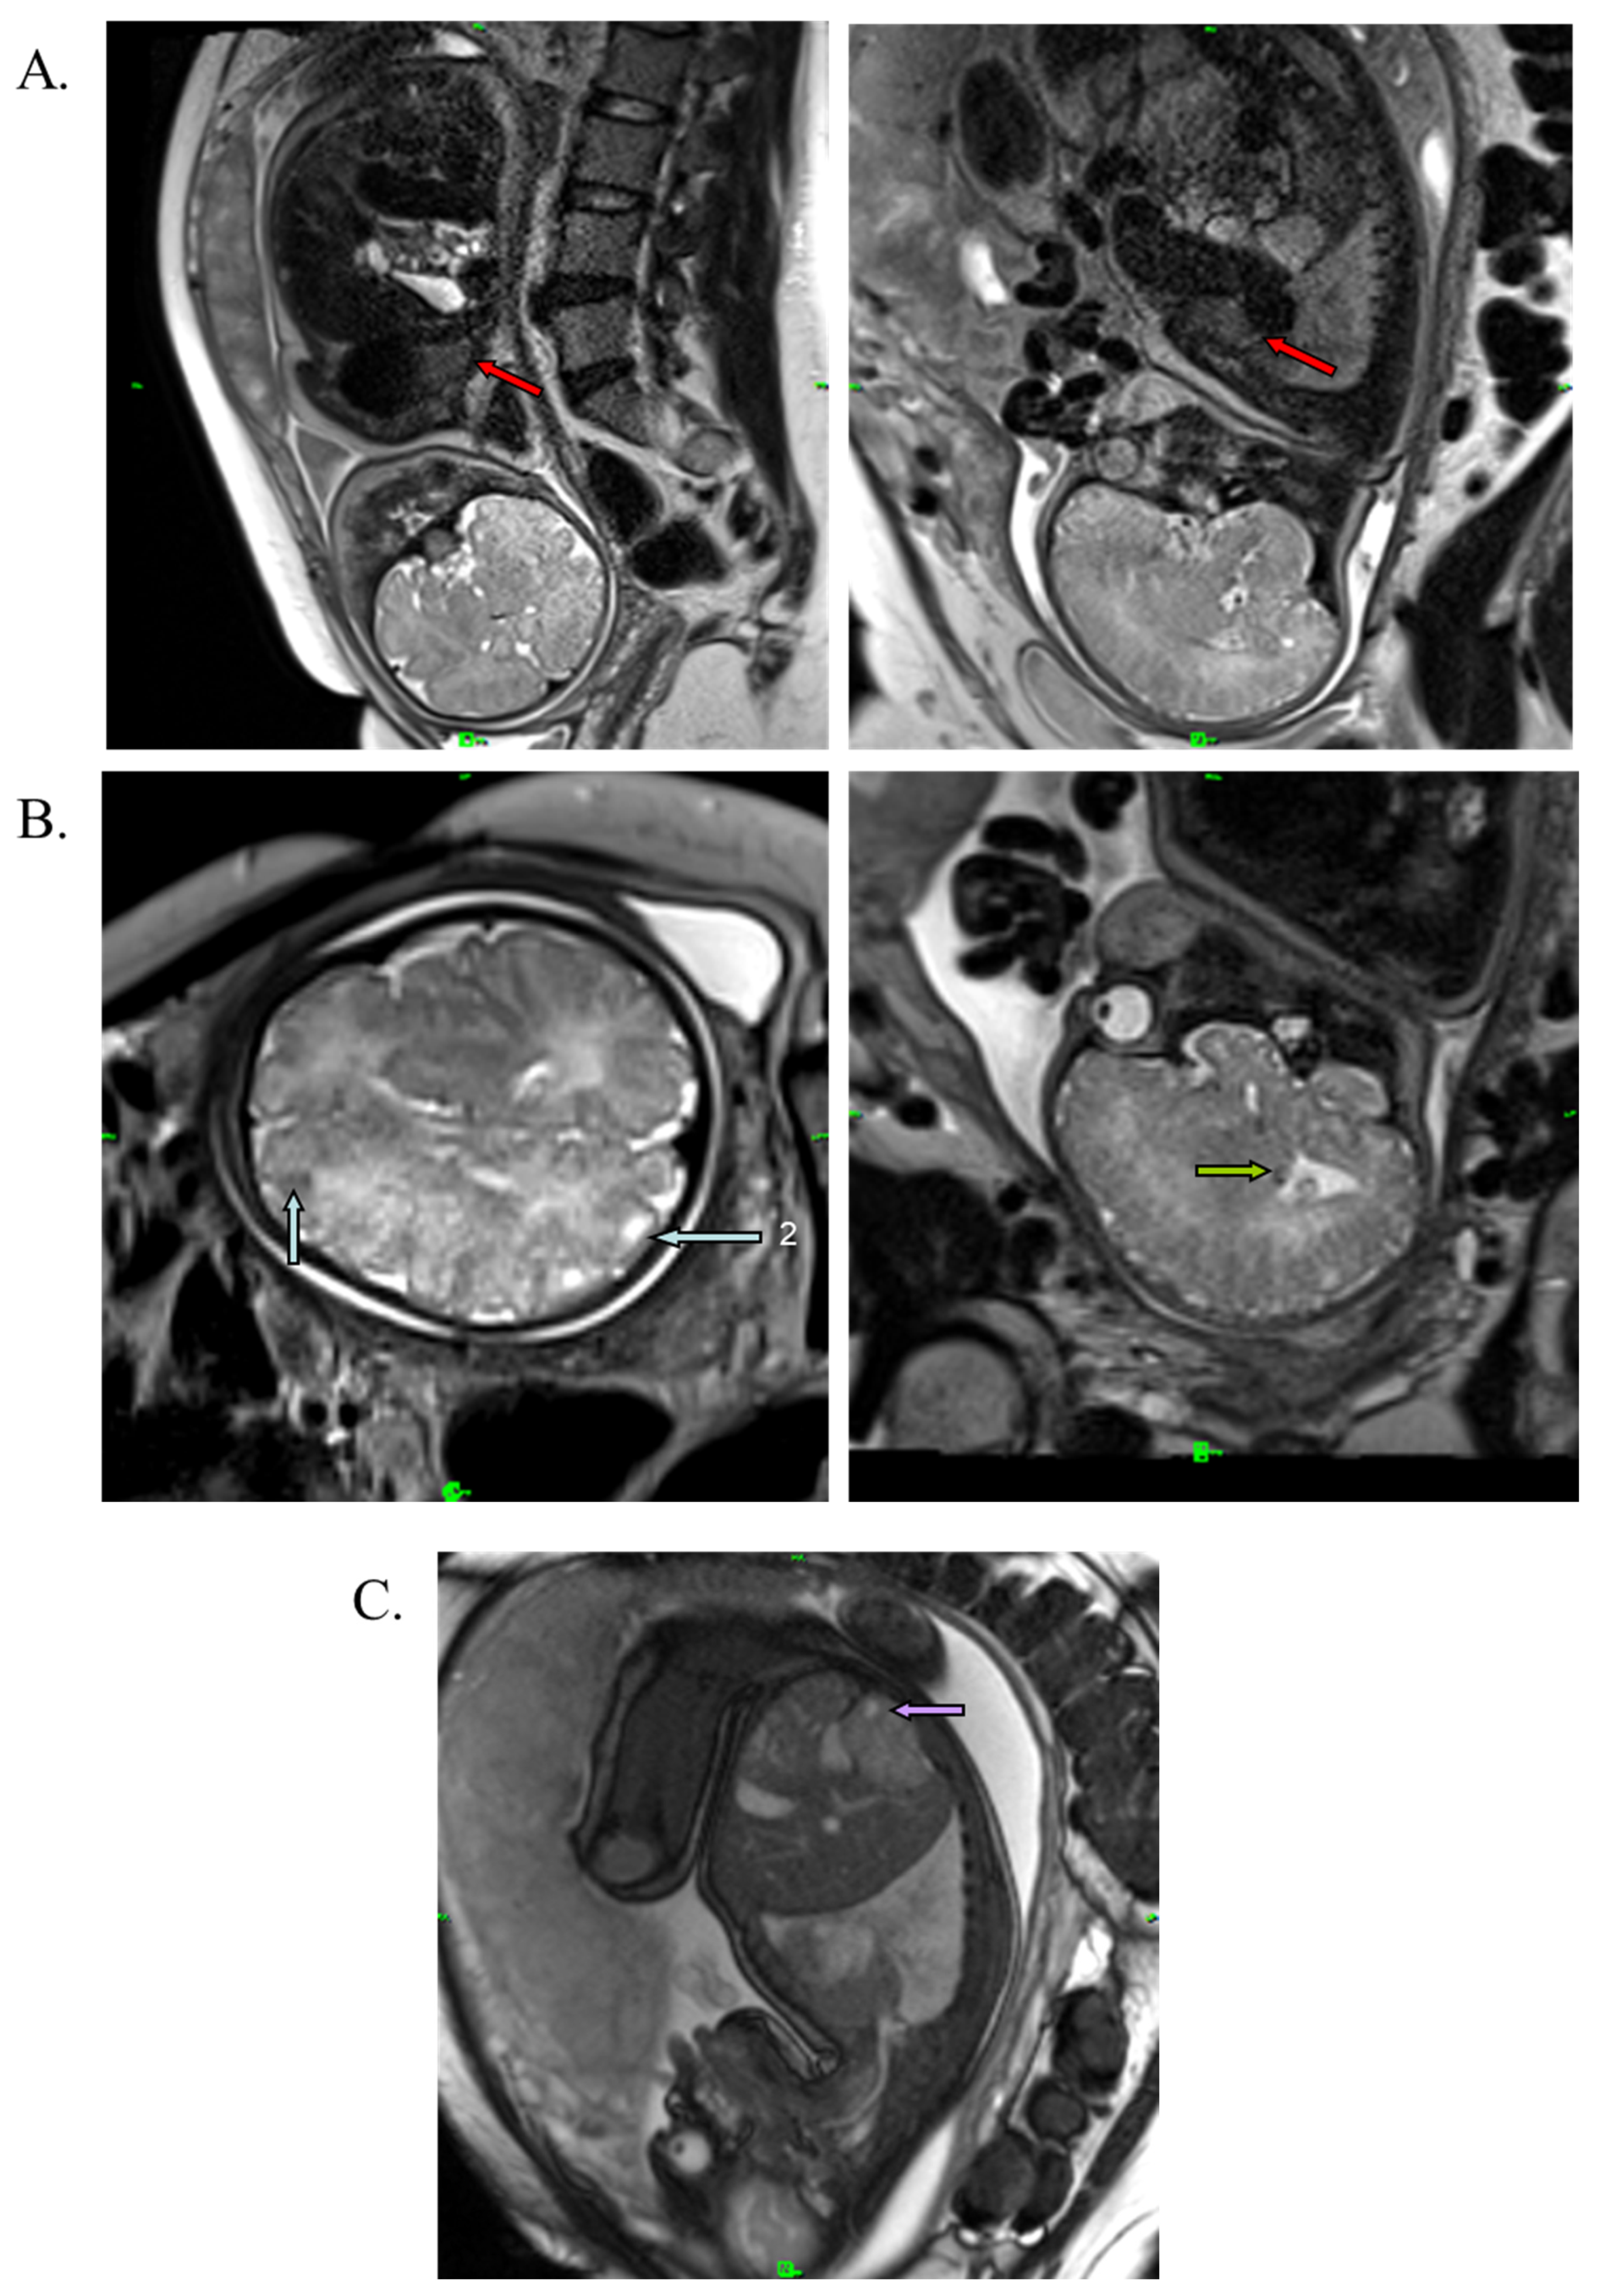

A medical team consisting of a cardiologist, clinical geneticist, obstetrician, and neonatologist decided to start oral immunosuppressant therapy for the mother (everolimus; Votubia). The goal of the treatment was to reduce the size of the rhabdomyoma, which lasted for five weeks. Oral everolimus was given daily. An initial dose of 10 mg/day everolimus was administered. The dose was adjusted to 5 mg/day from day 10 to set the 5–15 ng/mL target trough level (see Table S1). Blood values, including hemoglobin, leukocytes, leukocyte differentiation, thrombocytes, and CRP, were monitored during the treatment. All laboratory parameters were within the normal range. Everolimus reduced the size of the rhabdomyoma by almost half (20 × 20 × 33 mm) (Figure 3A). Everolimus was discontinued on day 36, two weeks before the scheduled cesarean section, to avoid complications and pre- and postnatal infection. The fetus and mother did not experience adverse events during the entire length of the treatment. Fetal MRI performed during the 38th week of gestation also revealed renal cysts in the fetus (Figure 3C).

Figure 3.

T2-weighted MRI image of the fetus at the 38th week of gestation. (A) Red arrows show cardiac rhabdomyoma in reduced size (20 × 20 × 33 mm). (B) Blue arrows show cortical tuber in the gyral core (2), and green arrows represent subependymal nodule in the brain. (C) Purple arrow shows the renal cyst.

The male infant was born at term by caesarean section with a birth weight of 3700 g (+0.67 SD), birth length of 52 cm (+1.11 SD) and a head circumference of 35 cm (+0.42 SD). This was the mother’s fourth pregnancy (G3, P1). The Apgar score was 9/10. Standard deviations (SD) for birth measurements were calculated using WHO standards [30]. After birth, the boy was monitored in a perinatal intensive care unit for one week. His laboratory parameters were normal. Cardiological examination revealed rhabdomyoma and mitral insufficiency, and the abdominal ultrasound examination suggested angiomyolipoma in the kidneys. The MRI performed at 2 months of age confirmed the findings of the perinatal examinations (Figure 4A). The MRI additionally revealed white-matter radial migration lines, presenting a straight band and nonspecific conglomerate foci (Figure 4B).

Figure 4.

T1-weighted axial MRI image of the brain and T2-weighted sagittal MRI image of the heart at 2 months of age. (A) Red arrows represent cardiac rhabdomyoma. (B) Blue arrows show cortical tubers in the sulcal island (1) and in the gyral core (2); green arrow represents a subependymal nodule. Brown and yellow arrows show white-matter radial migration lines: straight band (brown), nonspecific conglomerate foci (yellow).